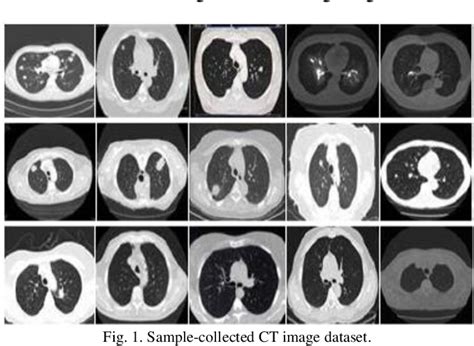

pdf lung cancer prediction and classification using adaboost data mining algorithm